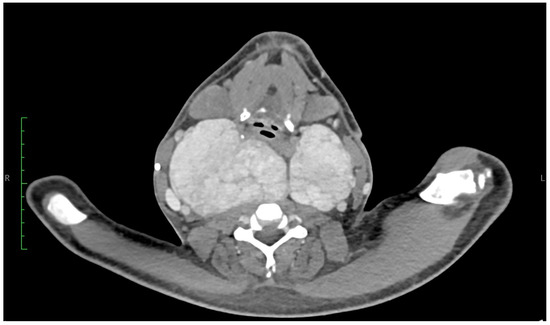

A Rare Case of Systemic Amyloidosis Involving the Thyroid in a Young Patient

by Oliwia Julia Kasprzak, Kamila Stępińska, Kaja Kiedrowska, Tomasz Błaszkowski, Aleksandra Kudrymska, Sylwia Sikora, Maciej Miernik and Maciej Romanowski

J. Clin. Med. 2025, 14(19), 6741; https://doi.org/10.3390/jcm14196741 - 24 Sep 2025

Thyroid amyloidosis is a rare condition associated with thyroid pathologies such as medullary carcinoma, papillary carcinoma, amyloid goitre, and benign lesions, with a clinically palpable goitre being exceptionally uncommon. As a result, many cases of benign thyroid enlargement caused by amyloid deposits remain [...] Read more.

Thyroid amyloidosis is a rare condition associated with thyroid pathologies such as medullary carcinoma, papillary carcinoma, amyloid goitre, and benign lesions, with a clinically palpable goitre being exceptionally uncommon. As a result, many cases of benign thyroid enlargement caused by amyloid deposits remain undiagnosed. A 28-year-old male patient noticed progressive neck circumference enlargement, voice alteration, decreased appetite, weight loss, dysphagia, fever, and night sweats. Fine-needle aspiration biopsy of the thyroid gland did not reveal the cause of the goitre. A total thyroidectomy was performed. Histopathological examination confirmed advanced thyroid amyloidosis. Full article

Show Figures

Figure 1